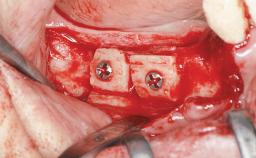

Ridge Preservation and Implant Placement for a Fixed Dental Prosthesis After a Car Accident

It is well known to clinicians that any removal of teeth will, over time, cause the dimensions of the alveolar ridge to be reduced by resorption of the bundle bone and by changes related to external modeling. This development is particularly evident in the crestal region with its thin buccal bone that consists of bundle bone almost entirely. The facial bone will rapidly resorb as blood supply from the periodontal ligament gets disrupted (Araújo and Lindhe 2005). There is no reason why traumatic tooth loss should not have the same consequences. It takes more than achieving implant osseointegration for a treatment outcome to be considered successful. No deficiency of bone or soft tissue is acceptable when an ideal esthetic outcome is the goal. Several articles (Sanz and coworkers 2011; Vignoletti and coworkers 2011) have reported on techniques of improving the alveolar ridge for implant treatment, notably focusing on protecting tissues from resorption.

Bone Augmentation Horizontal|Simultaneous|Sinus Floor Elevation|Staged